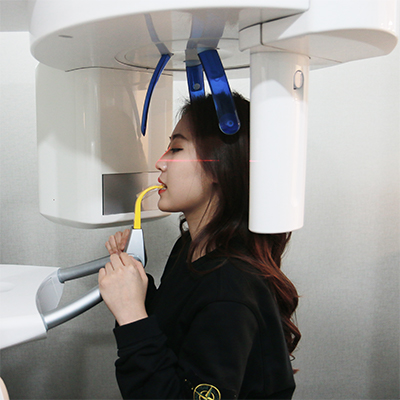

Diagnosis

Consultation

Plan Customized Treatment

Install Alignment Devices